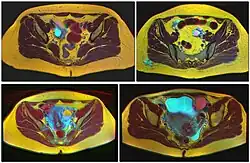

Ovarian cysts are usually diagnosed by pelvic ultrasound, CT scan, or MRI, and correlated with clinical presentation and endocrinologic tests as appropriate.[15] Ultrasound is the most important imaging modality, as abnormalities seen in a CT scan sometimes prove to be normal in ultrasound.[5][8] If a different modality is needed, then MRIs are more reliable than CT scans.[5]

Follow-up imaging in women of reproductive age for incidentally discovered simple cysts on ultrasound is not needed until 5 cm, as these are usually normal ovarian follicles. Simple cysts 5 to 7 cm in premenopausal females should be followed yearly. Simple cysts larger than 7 cm require further imaging with MRI or surgical assessment. Because they are large, they cannot be reliably assessed by ultrasound alone; it can be difficult to see posterior wall soft tissue nodularity or thickened septation due to limited ultrasound beam penetrance at this size and depth. For the corpus luteum, a dominant ovulating follicle that typically appears as a cyst with circumferentially thickened walls and crenulated inner margins, follow up is not needed if the cyst is less than 3 cm in diameter.[8] In postmenopausal women, any simple cyst greater than 1 cm but less than 7 cm needs yearly follow-up, while those greater than 7 cm need MRI or surgical evaluation, similar to reproductive age females.[16]

For multilocular cysts with thin septation less than 3 mm, surgical evaluation is recommended. The presence of multiloculation suggests a neoplasm, although the thin septation implies that the neoplasm is benign. For any thickened septation, nodularity, vascular flow on color doppler, or growth over several ultrasounds, surgical removal may be considered due to concern of cancer.[16]